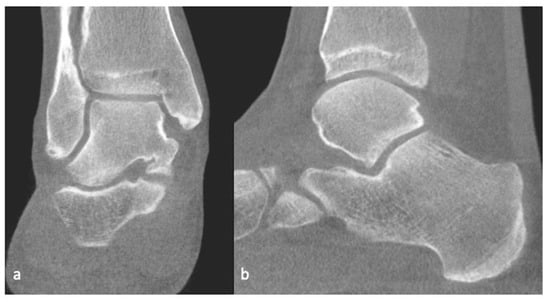

- Berndt Al Harty, M. Transchondral fractures (osteochondritis dissecans) of the talus. J. Bone Jt. Surg. Am. 1959, 41, 988–1020. [Google Scholar] [CrossRef]

- Anderson, I.F.; Crichton, K.J.; Grattan-Smith, T.; Cooper, R.A.; Brazier, D. Osteochondral fractures of the dome of the talus. J. Bone Jt. Surg. Am. 1989, 71, 1143–1152. [Google Scholar] [CrossRef]

- Loomer, R.; Fisher, C.; Lloyd-Smith, R.; Sisler, J.; Cooney, T. Osteochondral lesions of the talus. Am. J. Sport. Med. 1993, 21, 13–19. [Google Scholar] [CrossRef]

- Hepple, S.; Winson, I.G.; Glew, D. Osteochondral Lesions of the Talus: A Revised Classification. Foot Ankle Int. 1999, 20, 789–793. [Google Scholar] [CrossRef]

| Berndt and Harty (X-ray) | Loomer et al. [57] Modification (CT) | Hepple et al. [58] (MRI) |